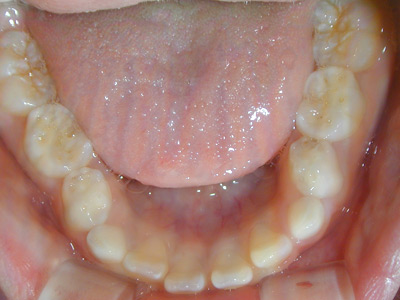

南粕谷在住 M.H様(32歳女性)

M.H様は矯正相談にて来院され下の前歯がガタガタであることを主訴に来院されました。

下顎前歯の叢生の改善のために部分矯正を希望されました。下顎の前歯群には中等度の叢生がみられます。

神経系の慢性疾患のためお薬の副作用の影響で歯肉の腫脹が目立っています。

むし歯の有無や歯周病の程度、修復物の状態などの口腔内検査を行い、

レントゲン写真、口腔内写真、正貌と側貌の写真撮影を行い診断のための資料を採取しました。

![]() |

下顎前歯の叢生の改善するためには上下顎前歯の接触が緊密なために上顎の前歯の矯正治療が必要となります。

臼歯関係、犬歯関係ともに1対2歯でよく咬んでいますので

咬み合わせの関係を壊すことなく上下顎の前歯の叢生を部分矯正で改善をめざします。

側貌から口元には緊張がなく突出を認めなかったので非抜歯で矯正治療できると患者様にはお伝えしました。

薬物の副作用の影響の歯肉の腫れは叢生の改善によりブラッシングが容易になると改善されることを期待します。

上下顎の前歯を前方へ移動させ、その状態により前歯のストリッピングを行うなどを計画します。

上顎の前歯部分の矯正治療を先行させます。上下顎前歯の接触状態をみてその後、下顎の小臼歯部までブレースを接着します。

部分矯正ですがブレースを接着する部位は咬み合わせの安定のために広範囲となります。

上顎のワイヤーをステップアップし、下顎にブレースが付くようになった時点で下顎に最初のワイヤーを装着します。

ストリッピングを行うことなく上下顎の前歯の叢生は改善されました。

上顎両側側切歯の歯肉の腫れは消退し、下顎前歯の叢生の改善により歯肉の腫れは消退傾向がみられます。

今後は上顎中切歯の歯間乳頭の腫れを軽減するためブラッシング指導と保定治療時のPMTCを継続する予定です。

矯正歯科治療で歯列が改善されたことで歯口清掃が容易になり、常用薬剤の副作用である歯肉腫脹は軽減されています。

治療費用:50万円

動的治療期間:1年6か月